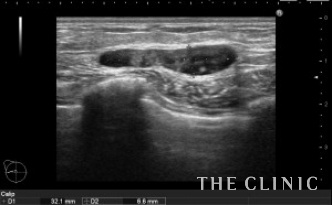

左が充実性のしこりです。右がオイルシストです。